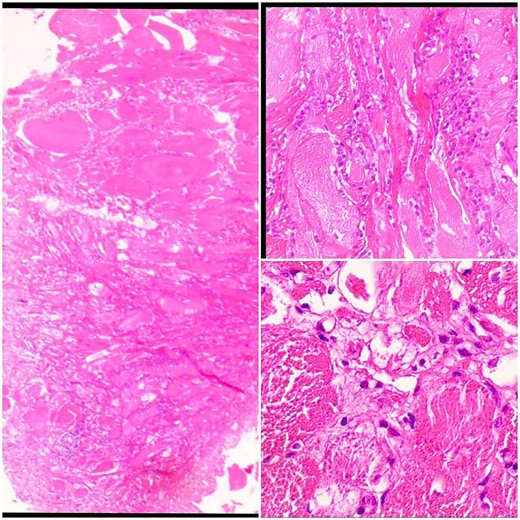

The muscle biopsy was performed through a 2-cm incision above the belly of the Flexor Digitorum Brevis muscle, where the muscle fibers appeared visually in pale pink with hypertrophy and the absence of flexibility, but there was an adhesion of the muscle fibers to each other without the presence of damage to those fibers. Histopathology shows degeneration and regeneration of muscle fibers with focal fibrosis associated with interstitial inflammation and focal neurogenic changes. The inflammation consists prominently of eosinophil cells and in some sections there were B cells or CD123+ dendritic plasma cells without the presence of tumor cells (Fig. 6).

Sections show skeletal muscle fibers infiltrated by inflammatory cells.

We are pleased to extend our thanks to Dr. Habib Jarboa for his assistance by providing us with a description of the histopathological sample and a simple explanation that is understandable to the reader at the microscopic level.